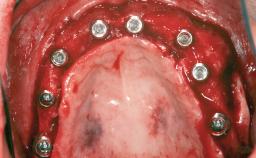

Iliac and Calvarial Bone Blocks for Onlay Grafting of a Severely Resorbed Edentulous Maxilla

A 45-year-old woman with a completely edentulous maxilla was referred to evaluate the possibility of rehabilitation with an implant-supported prosthesis. This patient was healthy and a non-smoker. She had been wearing a maxillary complete denture opposing a natural mandibular dentition since her twenties. This situation had resulted in progressive resorption of the alveolar ridge, repeatedly creating a need for relining the denture. Twenty years later, despite multiple adaptations and the use of “glues” the denture was unstable and causing the patient psychological and functional discomfort.

# of Implants 8

Bone Augmentation Horizontal|Sinus Floor Elevation|Staged|Vertical

Augmentation Materials Autogenous chips|Autogenous block(s)